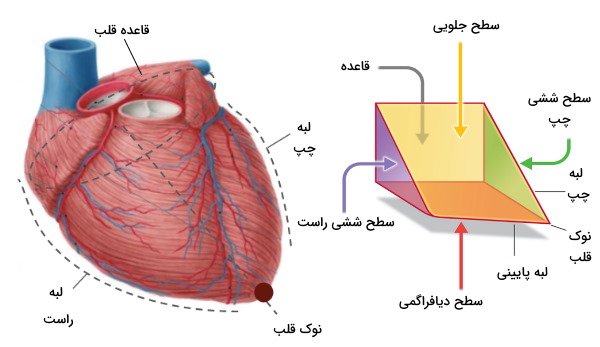

آناتومی قلب

قلب اندامی ماهیچهای است که وسط قفسه سینه قرار دارد. این اندام شبیه مخروطی چهار وجهی است که روی یکی از ضلعهای کناری قرار گرفته است. به همین دلیل قاعده آن سمت دیواره پشتی قفسه سینه و نوک آن سمت دیواره جلویی قفسه سینه قرار دارد. آئورت یکی از سرخرگهای اصلی قلب است که شاخههای آن خون را به تمام بافتها بدن، از سر تا انگشتان پا انتقال میدهند. قلب از پنج سطح (سطح قاعدهای (پشتی)، دیافراگمی (پایینی) و جناغی-دندهای (جلویی) و ششی راست و چپ) و چهار لبه تشکیل شده است.

- لبه راست: این لبه بخش کوچکی از دهلیز راست، بین بزرگسیاهرگ بالایی و پایینی است.

- لبه چپ: این لبه از بطن چپ و بخش کوچکی از دهلیز چپ تشکیل شده است.

- لبه بالایی: این لبه از رگهای بزرگ و دهلیزهای راست و چپ تشکیل شده است.

- لبه پایینی: این لبه از بطن راست و چپ تشکیل شده است.

بخش داخلی قلب به دو حفره بالایی دهلیز و دو حفره پایینی بطن تقسیم میشود. دهلیزها، حفرههای قاعده قلب (بالا) و بطنها حفرههای نوک قلب (پایین) هستند. سپتومها یا تیغههای ماهیچه دو دهلیز (سپتوم بیندهلیزی) و دو بطن (سپتوم بینبطنی) را از هم جدا میکنند. دریچههای قلب بین این حفرهها قرار دارند و جریان خون بین آنها را کنترل میکنند.